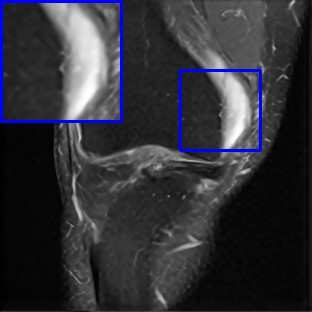

Limited by imaging systems, the reconstruction of Magnetic Resonance Imaging (MRI) images from partial measurement is essential to medical imaging research. Benefiting from the diverse and complementary information of multi-contrast MR images in different imaging modalities, multi-contrast Super-Resolution (SR) reconstruction is promising to yield SR images with higher quality. In the medical scenario, to fully visualize the lesion, radiologists are accustomed to zooming the MR images at arbitrary scales rather than using a fixed scale, as used by most MRI SR methods. In addition, existing multi-contrast MRI SR methods often require a fixed resolution for the reference image, which makes acquiring reference images difficult and imposes limitations on arbitrary scale SR tasks. To address these issues, we proposed an implicit neural representations based dual-arbitrary multi-contrast MRI super-resolution method, called Dual-ArbNet. First, we decouple the resolution of the target and reference images by a feature encoder, enabling the network to input target and reference images at arbitrary scales. Then, an implicit fusion decoder fuses the multi-contrast features and uses an Implicit Decoding Function~(IDF) to obtain the final MRI SR results. Furthermore, we introduce a curriculum learning strategy to train our network, which improves the generalization and performance of our Dual-ArbNet. Extensive experiments in two public MRI datasets demonstrate that our method outperforms state-of-the-art approaches under different scale factors and has great potential in clinical practice.